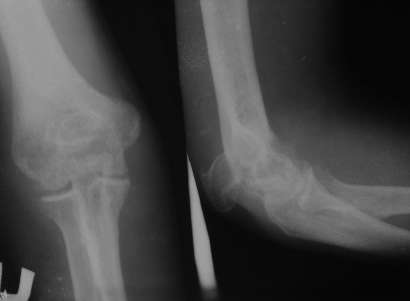

Perelom loktegovo otrоstka

Bolnoy 4 mesyatsa nazad paluchil travmu

Za medetsinskoy pomotschyu ne obratilsya. Cherez 4 mesyatsa gospitalizirovan dlya operatsiyi. Moy plan nalojit apparat Ilizarova s pastepennoy kompressiyey v oblasti pereloma.